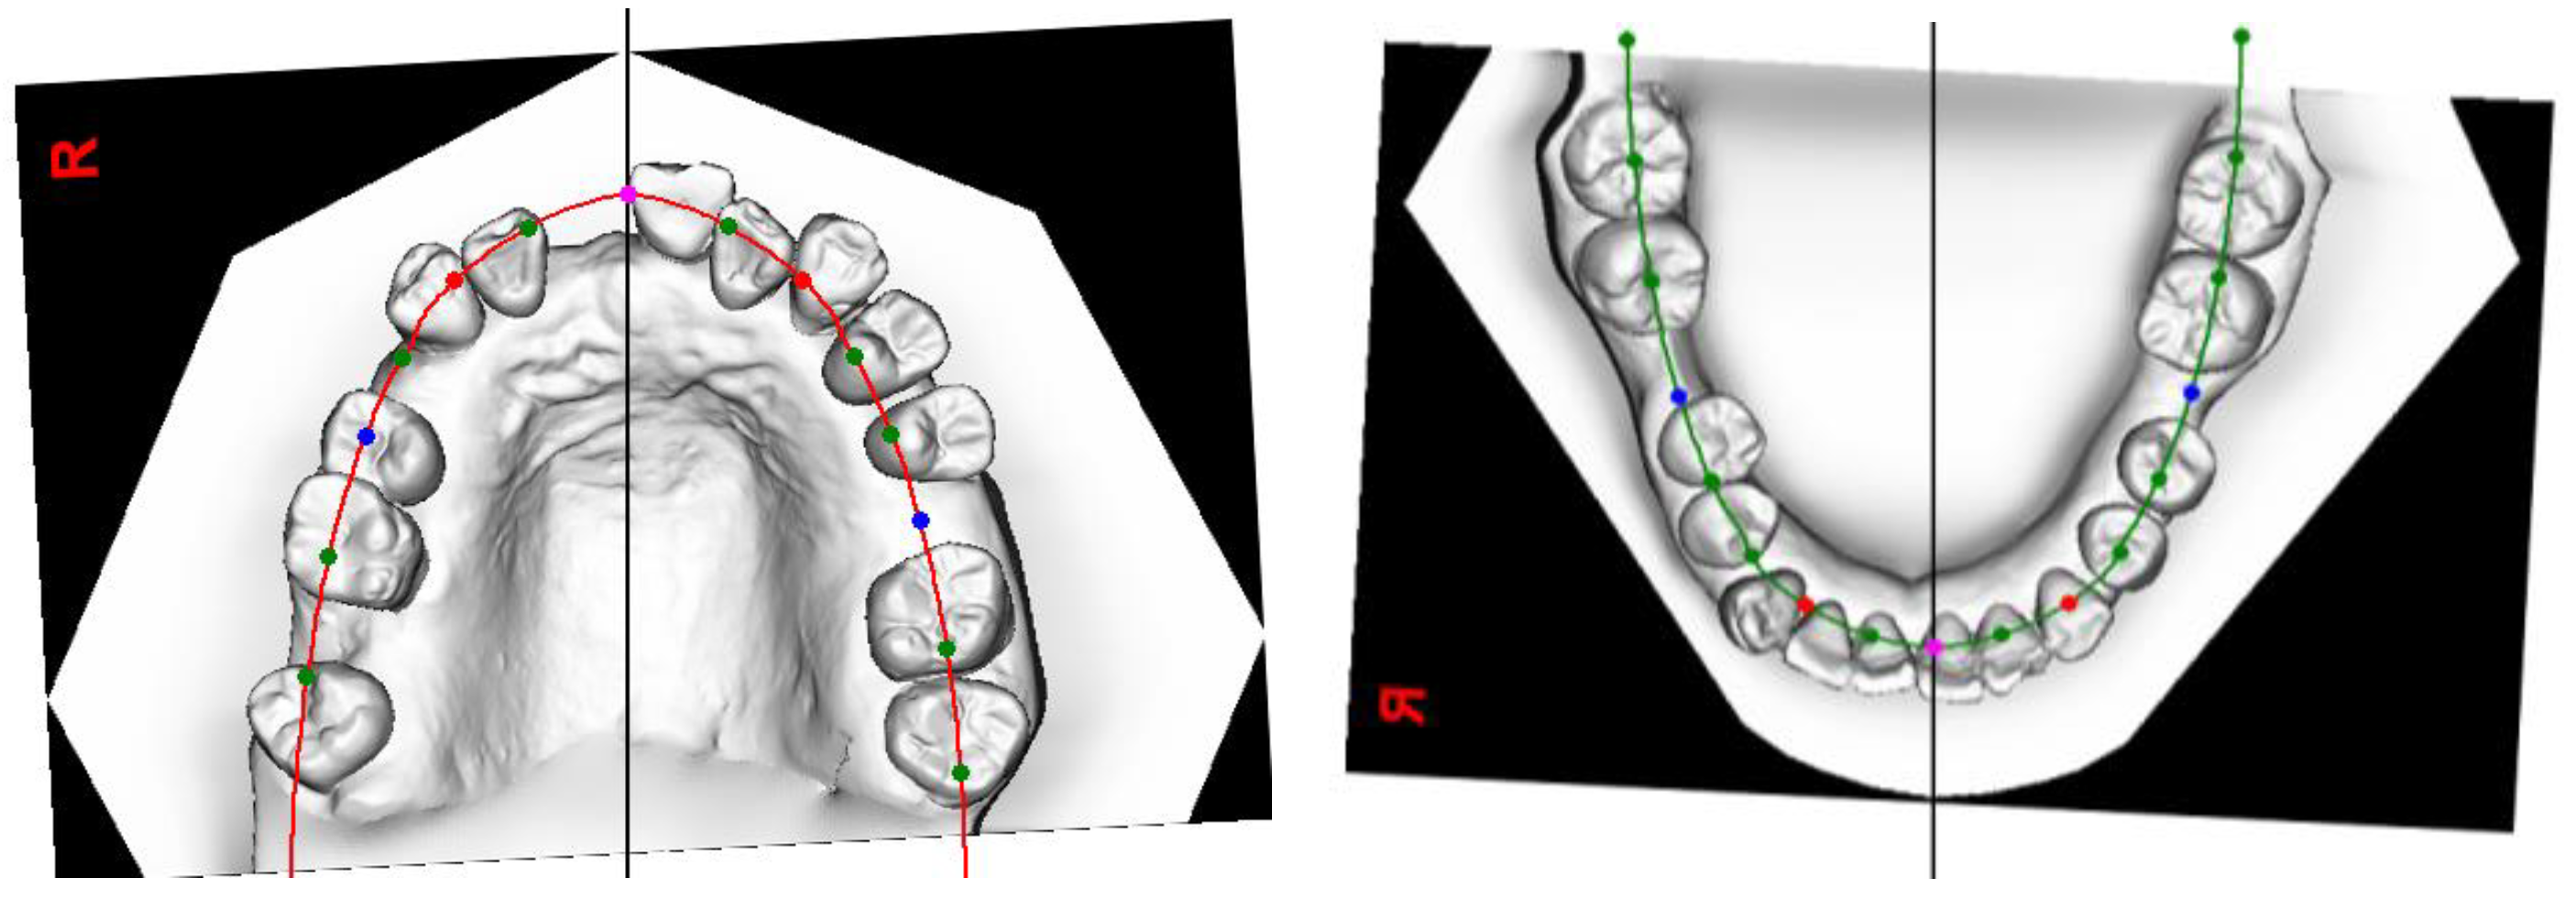

- As teeth 24 and 25 were significantly buccally displaced, sectional cantilever mechanics were used rather than direct bonding of the entire upper arch. There were two reasons for this. The first reason was to avoid creating unfavourable force systems on the other teeth due to the buccally displaced positions of teeth 24 and 25. Bonding brackets onto all upper teeth and engaging them with a straight wire could have resulted in an abnormal or skewed arch form. The second reason was that tooth 16 had a poor prognosis and was to be extracted in the future. Therefore, we decided to use tooth 16 as free anchorage to bring teeth 24 and 25 into the planned archform with cantilever mechanics, before proceeding with straight wire mechanics.

- (3.4.2)

- During the alignment and levelling stage, tooth 35’s crown was displaced distally and rotated disto-bucally, so a box loop capable of delivering the desired magnitude of force and precisely regulating the force direction was used. The box loop increased the total amount of wire between brackets of teeth 34 and 35, which produced a reduced load–deflection ratio and a greater range of action than any other loop type [41]. Furthermore, as the box loop was composed of a series of vertical and horizontal levers contoured to provide a short section of archwire that was freely movable in all planes in which it was activated, we used it to tip the crown of tooth 35 mesially and rotate tooth 35 mesio-lingually [41]. Moreover, sufficient anchorage was provided by the relatively rigid, continuous wire portion adjacent to the box loop, spanning from teeth 34 to 45, which effectively differentiated the active and reactive units.